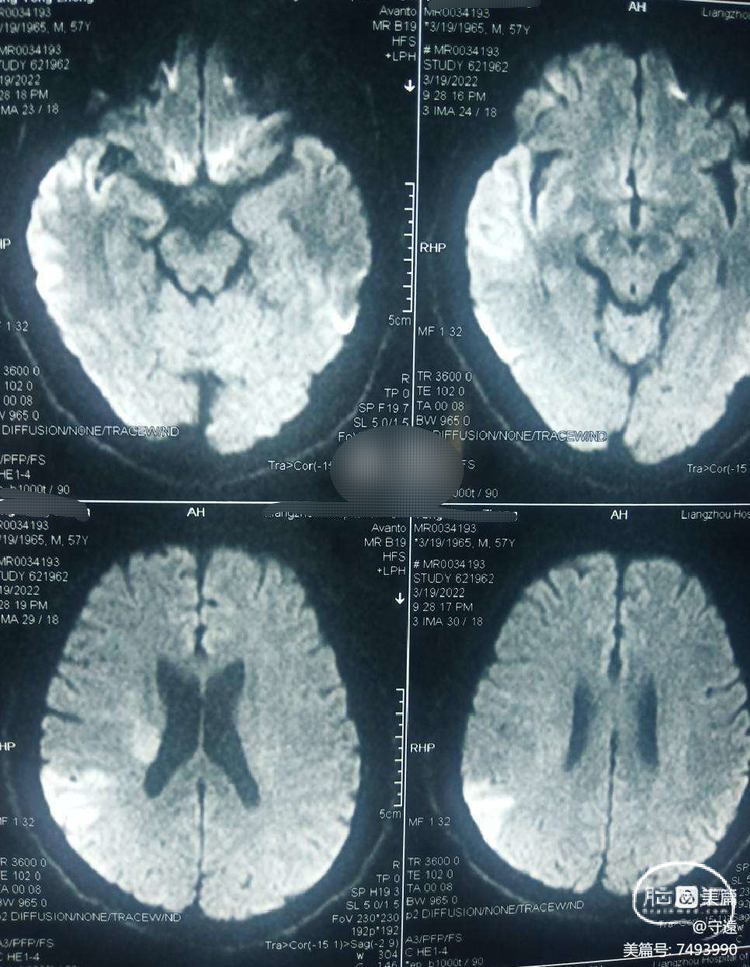

患者男性,57岁。

房颤,"突发左侧肢体失动2小时"入院。

左侧上下肢肌力1级。

NlHss评分9分。

CT无出血,核磁共振:DWⅠ显示右侧颞枕顶大片状高密度。考虑为大血管闭塞(心源性血栓可能)。